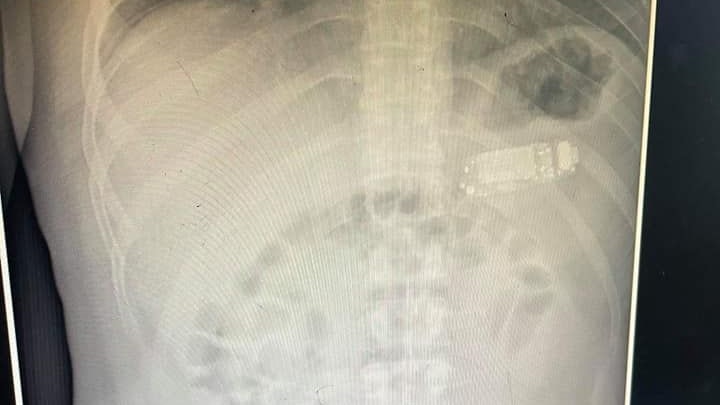

Die Ärzte in Pristina staunten nicht schlecht, was sie auf dem Röntgenbild sahen: Der Mann hatte ein Handy verschluckt!